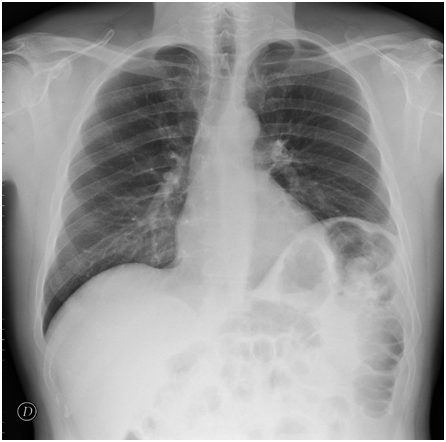

During standard preoperative workout, a chest X-ray (CXR) was performed, showing elevation of the left diaphragm due to splenodiaphragmatic colonic interposition (Figure 1). This finding raised concern about possible problems for intraoperative ventilation in steep Trendelenburg posture together with pneumoperitoneum. The situation was discussed with the patient, who was informed that a conversion to open surgery could have been possible in case of gas exchange problems due to the hemidiaphragmatic elevation.

Figure 1 Chest X-ray showing elevation of the left hemidiaphragm due to splenodiaphragmatic colonic interposition.